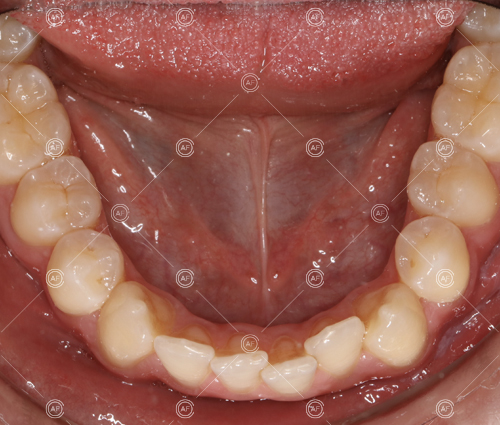

about this case…MH presented with class 1 incisors on the class 1 skeletal base with a slightly increased vertical proportion. She had severe crowding in the upper arch and moderate crowding in the lower. Due to the crowding in the lower arch, the lower centre line was off to the left by 2mm.

Buccal segments were essentially class 1 on the right hand side and a full unit class 2 on the left. This is due to buccal exclusion of the upper left 3 and mesial drift of the upper buccal segment.